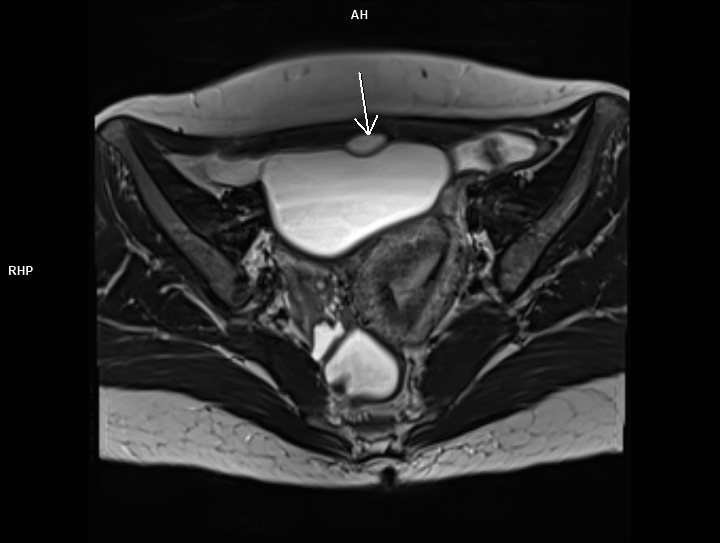

Figura 1: axial T2

Discuţie caz nr 83: chistul de uracă apare datorită faptului ca uraca nu s-a inchis complet în timpul dezvoltării fetale si este un buzunar umplut cu lichid; uraca este o structură embriologică normală care leagă vezica fetală de cordonul ombilical. Majoritatea chistelor uracale sunt asimptomatice, însă uneori se pot infecta şi pot provoca complicații: simptome ale tractului urinar, hematurie sau o masă palpabilă.

Chistele de uraca se datorează faptului că uraca nu s-a închis în primul trimestru de sarcina; pot fi descoperiri întâmplătoare la examinările imagistice sau se pot complica.